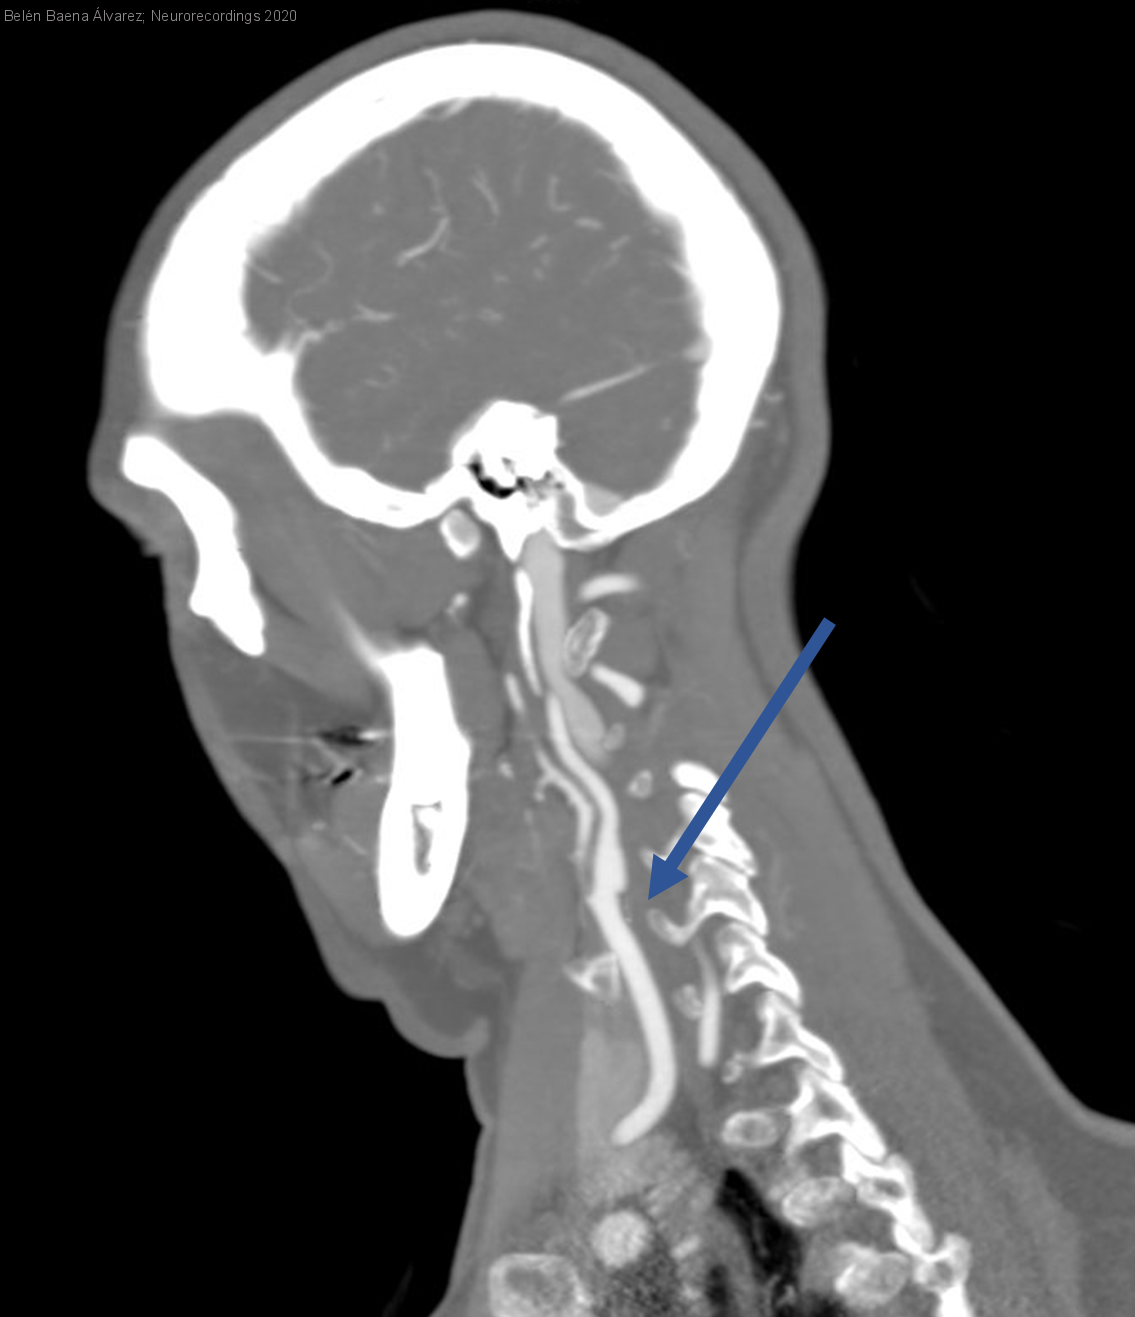

Diagnóstico final: Carotid web (displasia fibromuscular atípica)

Mujer de 58 años que acude a nuestro centro por cuadro de torpeza de la mano izquierda y disartria de 10 min de duración. A nuestra valoración la paciente se encontraba neurológicamente asintomática con TA...